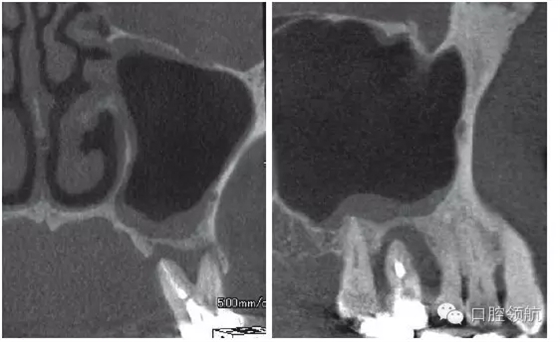

患者,78歲,男性 ,因6 牙齦腫脹來院,檢查見牙根周圍因牙槽骨缺損表現(xiàn)為透過影像(圖1)。在制訂治療計劃時,對于因重度牙周炎、慢性根尖周炎、牙根折斷等原因?qū)е碌难例X缺失需要行上頜竇底提升術的病例,不能單純考慮缺牙區(qū),要同時考慮鄰牙狀態(tài),并用CBCT確認上頜竇底黏膜是否有增厚,這是非常重要的。該病例,根據(jù)CBCT能夠觀察到上頜竇底黏膜增厚,拔牙即刻植入感染幾率較高。計劃拔牙后4~8周,拔牙窩牙齦上皮愈合但拔牙窩未消失時(拔牙后早期植入)植入種植體(圖2)。

圖1 CBCT影像確認是由6 引起的上頜竇底黏膜增厚。

拔除(左上第六顆牙)后,抗生素(500mg)口服1周。術后4周的CBCT顯示,上頜竇黏膜增厚明顯改善(圖3)。

圖3 拔牙后4周,上頜竇黏膜增厚消失,但仍有殘留牙槽窩。